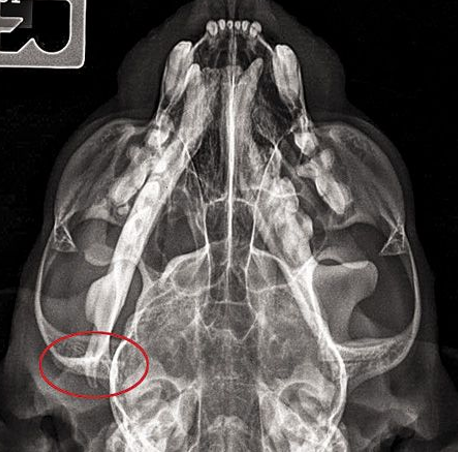

15

Q

A

fractured mandibula in oblique views

in the right mandibula view you can barely see the fracture due to superimposition of structures so capture both mandibula on their own image.